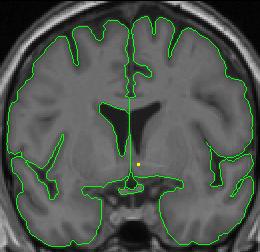

The histogram method is used to create outlines for the lateral ventricles. One histogram is needed to determine the CSF/white matter border, and another is used to define the CSF/gray matter border. A separate circle and histogram should be generated for each ventricle.

lateral-ventricle